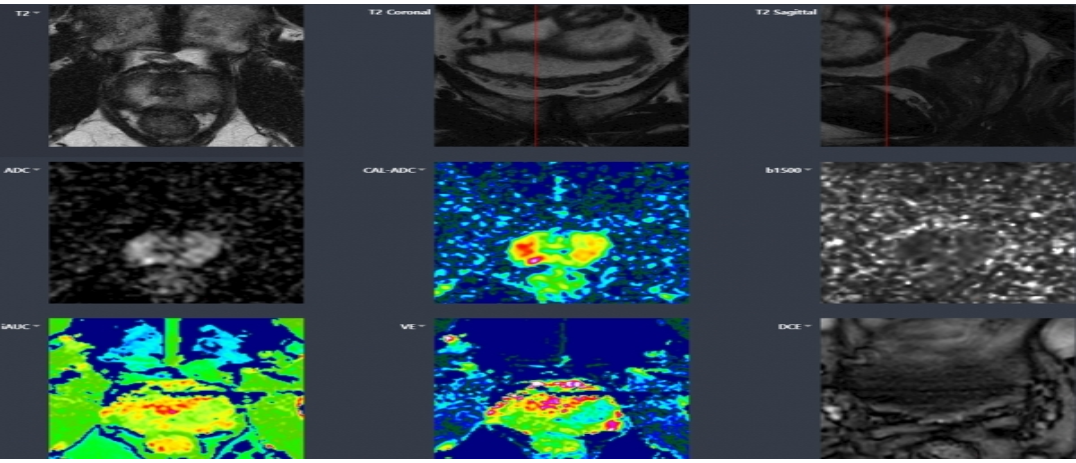

전립선암과 같이 고령화와 서구형 식습관의 증가로 환자가 늘고 있는 암종에서도 AI 진단 솔루션이 활발히 도입되고 있습니다 5. 예를 들어, ‘메디허브 프로스테이트’나 ‘딥디엑스 프로스테이트’ 같은 AI 기반 전립선암 진단 솔루션은 MRI나 조직 생검 이미지를 분석해 암 의심 부위를 시각화하고, 불필요한 조직검사 횟수를 줄여 환자의 고통을 획기적으로 줄였다는 평가를 받고 있습니다.